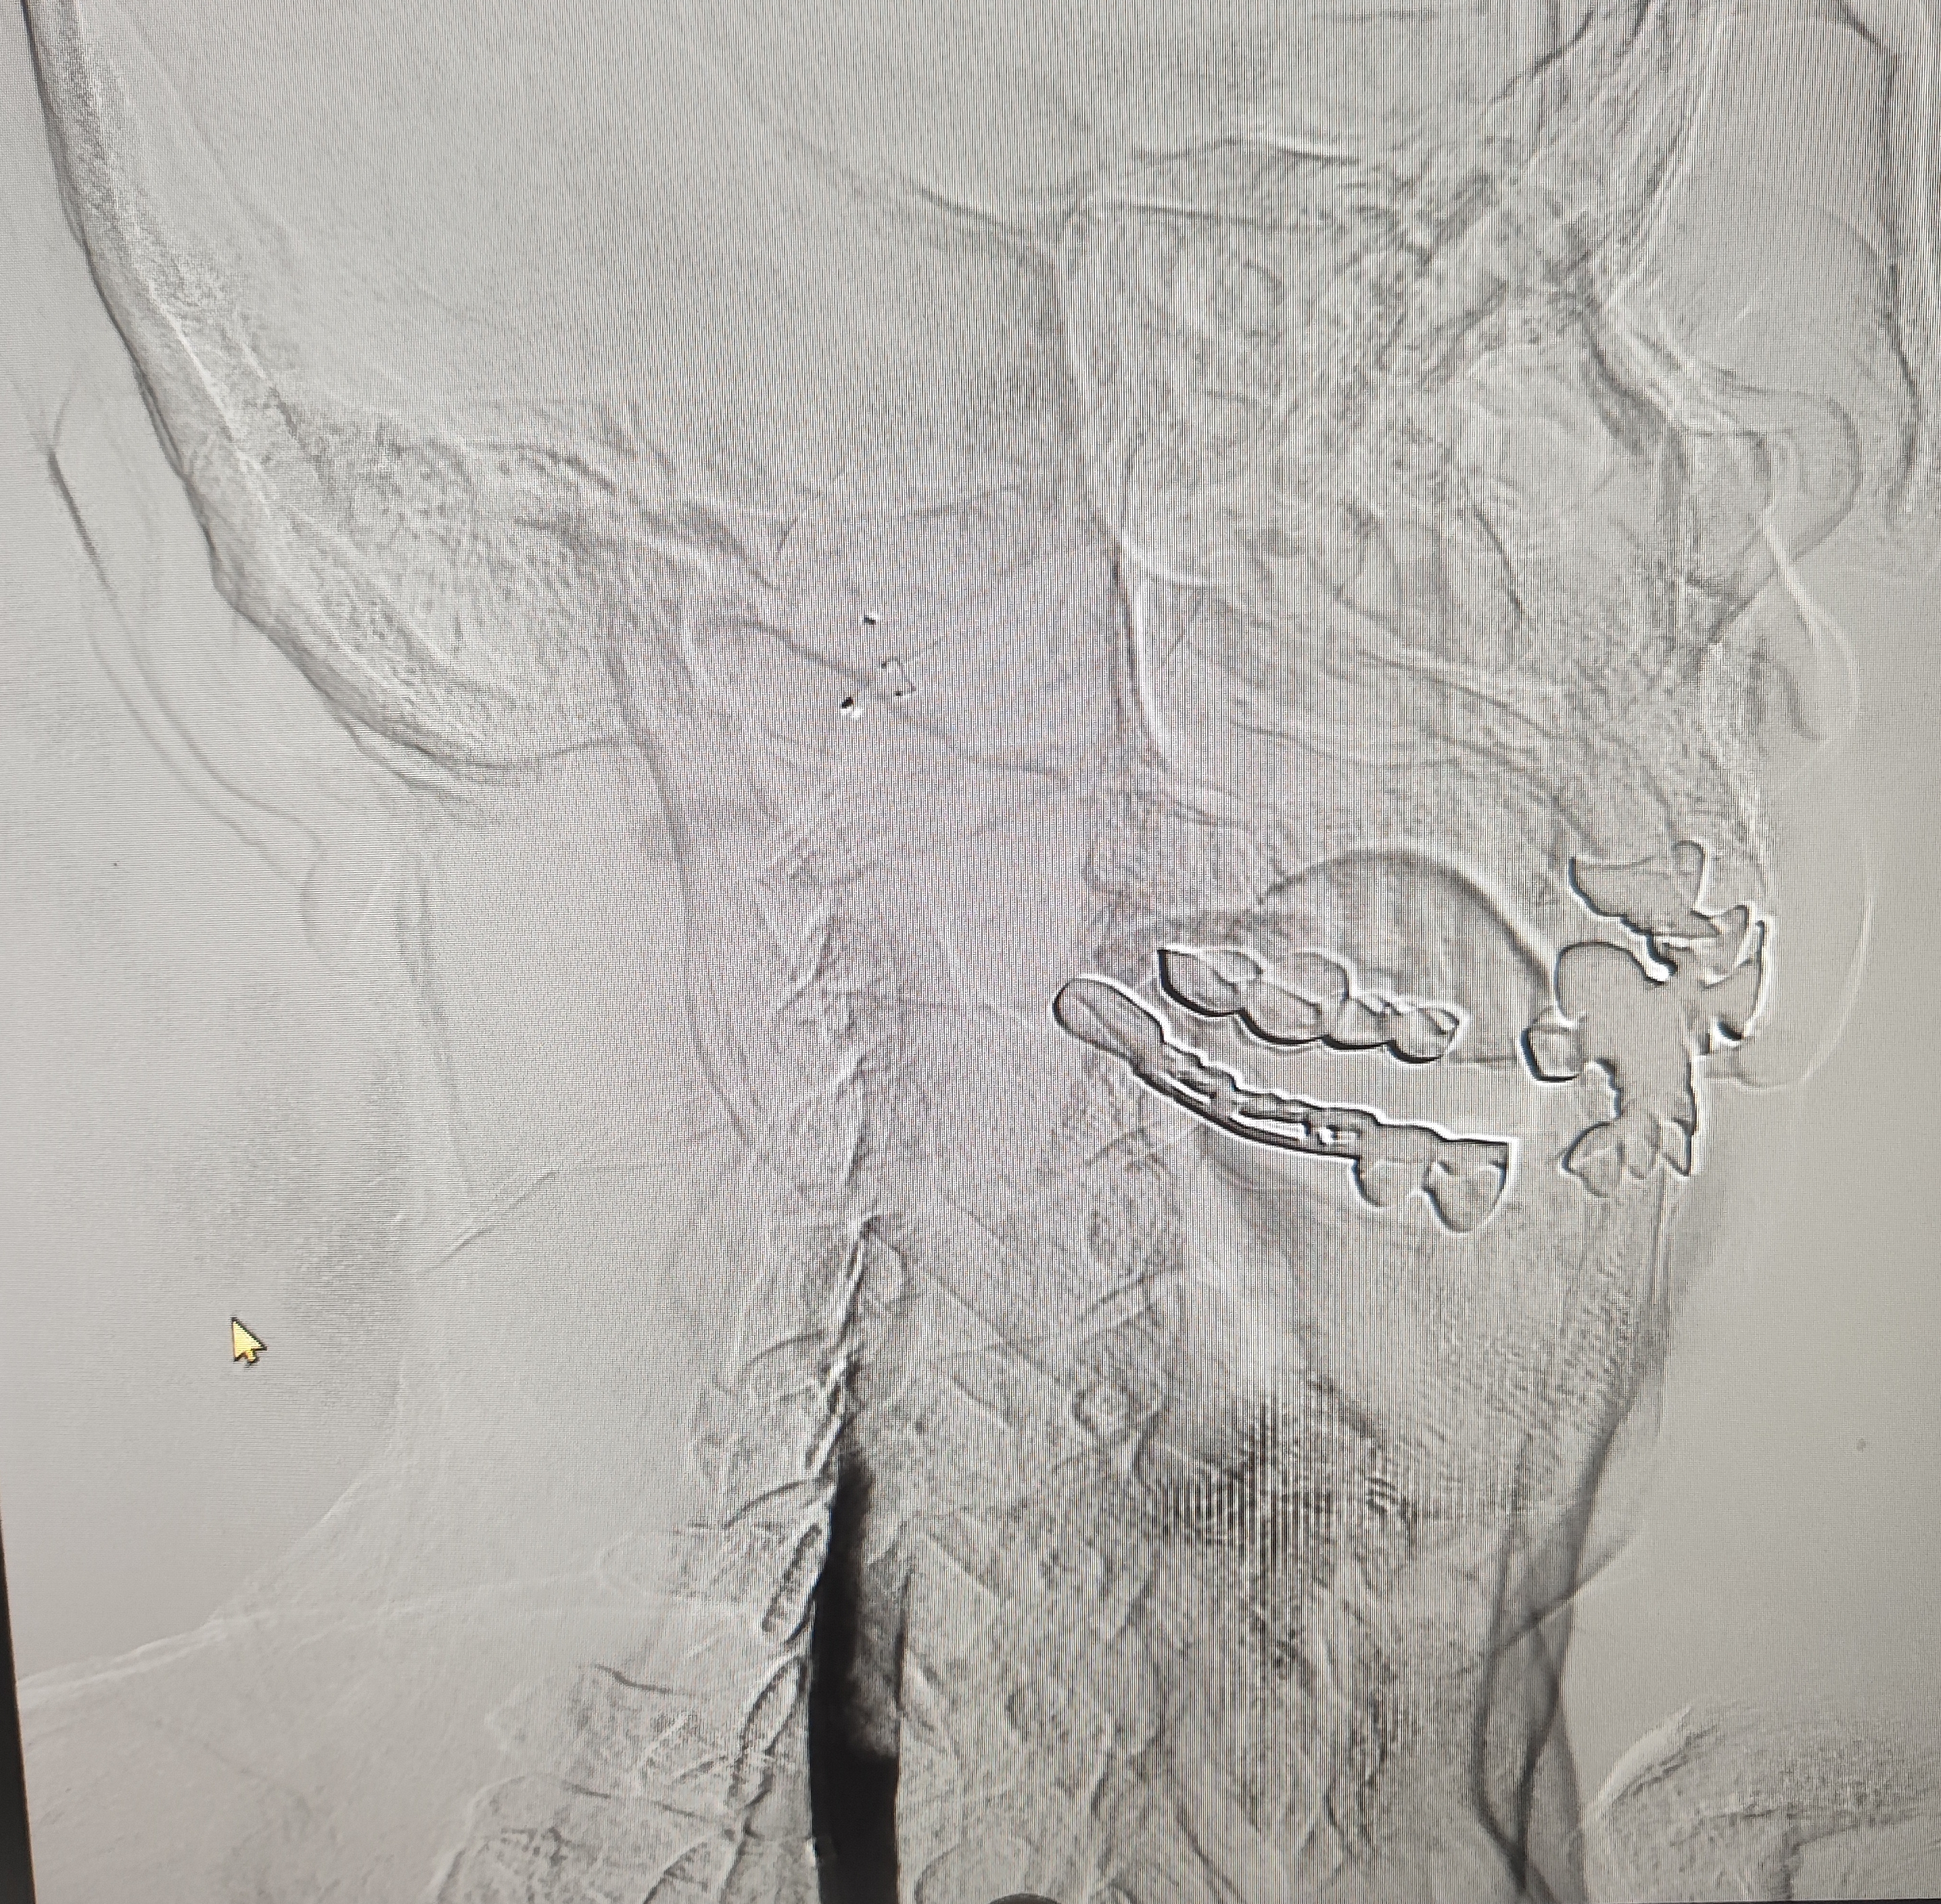

颈总巨大斑块急性闭塞的血管内治疗(双颈动脉支架桥接+支架释放后掉斑块,抽吸取栓)

急诊上台。